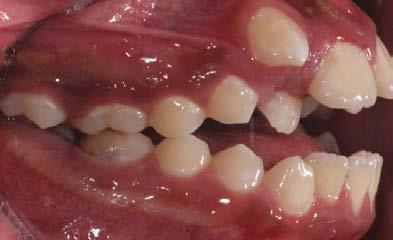

Estudio de caso

El paciente se presentó después de varios años de sufrir una herida traumática en sus dientes anterio res superiores. Las piezas 11 y 21 tenían varias fracturas, así como el borde incisal de la pieza 12. Por lo que él deseaba mejorar su estética bucal, y yo quería asegurarme de restaurar la funcionalidad y resisten cia también. El paciente necesitaba completar su tratamiento en un cor to periodo de tiempo, por ello debí realizar ajustes en mi flujo de traba jo. (Figura 1).